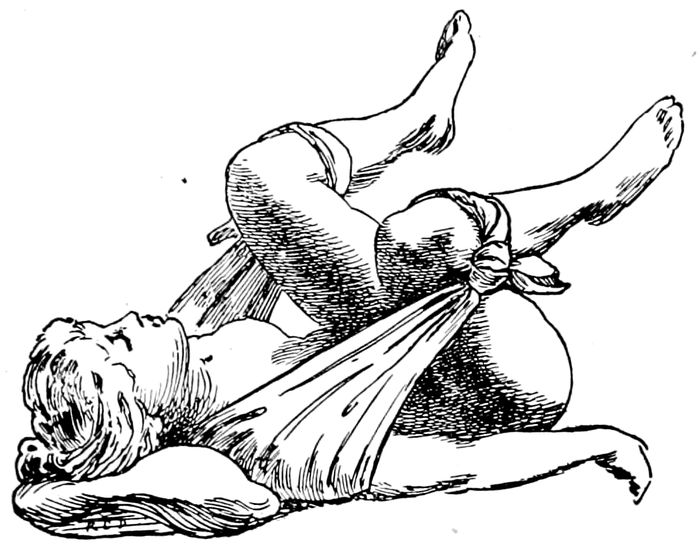

| 16102. |

The exaggerated lithotomy position obtained with a sheet sling |

237 |

| |

| 103. |

The improvised Trendelenburg position |

237 |

| |

| 104. |

The dorsal position with stirrups |

238 |

| |

| 105. |

Dorsal position across the bed |

239 |

| |

| 106. |

Flexed dorsal position with feet on the table |

240 |

| |

| 107. |

The Sims position |

241 |